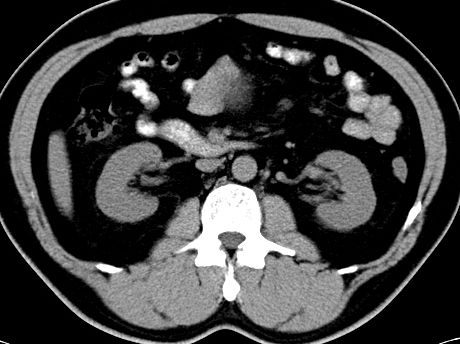

(腹腔)神经鞘瘤

男,48岁,间断性下腹不适1年。

手术探查

:距回盲部28厘米处肠系膜根部可见5*7cm左右包块,质中等硬度,活动度尚可,肝、胆、胰、脾肾未见明显异常。

病理

:(腹腔)

神经鞘瘤

,伴出血、坏死及囊性变,伴淋巴结反应性增生。

免疫组化结果

:sma(-), desmin(-), cd117(-), s-100(+++), nf(-),vimentin(+++).